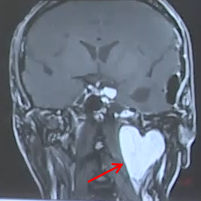

我的脑子里有颗爱心?这是肿瘤危险“示爱”

眼前这个这颗形状酷似爱心的颅底肿瘤,“爱”得令人窒息!请停止继续发散你的“爱”。